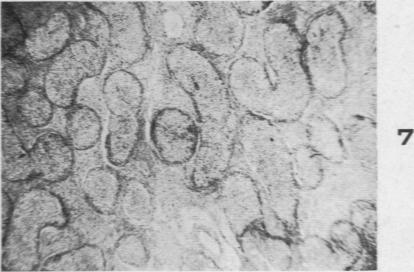

The Histopathology of Acute Mumps Orchitis.

Am J Pathol. 1947 Jul;23(4):637-51.